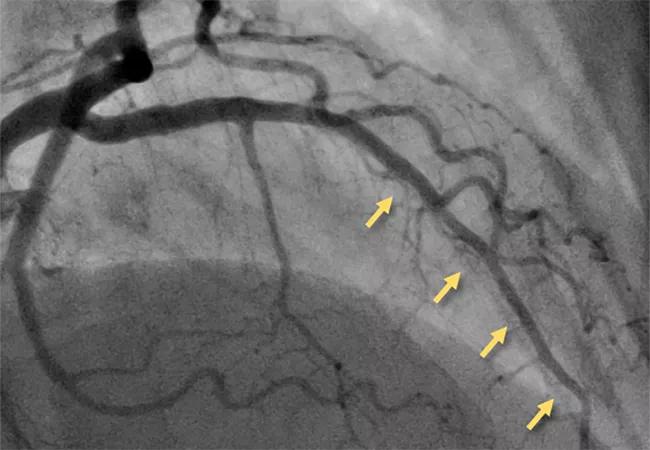

angiogram showing microvascular disease

Much-needed attention to microvascular disease

One traditionally overlooked subpopulation of CAD patients includes those with microvascular disease, or ischemia with non-obstructive coronary artery disease (INOCA). Cleveland Clinic’s long-standing interest in INOCA grew in late 2020 when Khaled Ziada, MD, joined the Section of Interventional Cardiology, where he is one of three staff cardiologists with a specialty interest in the condition.

“We consider INOCA when patients present with angina but have little or no evidence of plaque in the coronary arteries,” Dr. Ziada explains. “Although it is quite common, there’s a significant need for better diagnosis, which is the foundation of proper management. Cleveland Clinic is one of just a few centers in the middle of the country with expertise in INOCA diagnosis and treatment.”

In the three years from 2021 through 2023, Cleveland Clinic conducted diagnostic testing for suspected INOCA in over 400 patients. Patients are evaluated via specialized catheterization lab testing for the two major forms of INOCA, microvascular angina and vasospastic angina, with most patients tested for both.